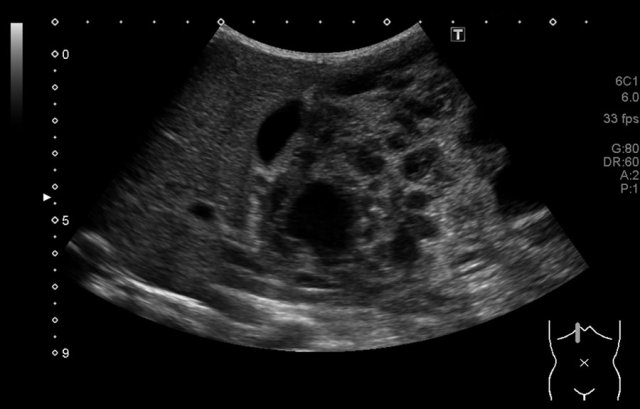

The image is of a two-year-old boy, who presented with a painless swelling of the abdomen. Ultrasound shows a large multicystic mass at the caudal side of the liver.

Continue with the MRI.

T1 weighted fat suppressed coronal MRI provides a better overview of the liver lesion, which was almost 2 kilograms at resection.

Pathology showed a mesenchymal hamartoma. No further follow-up was necessary.